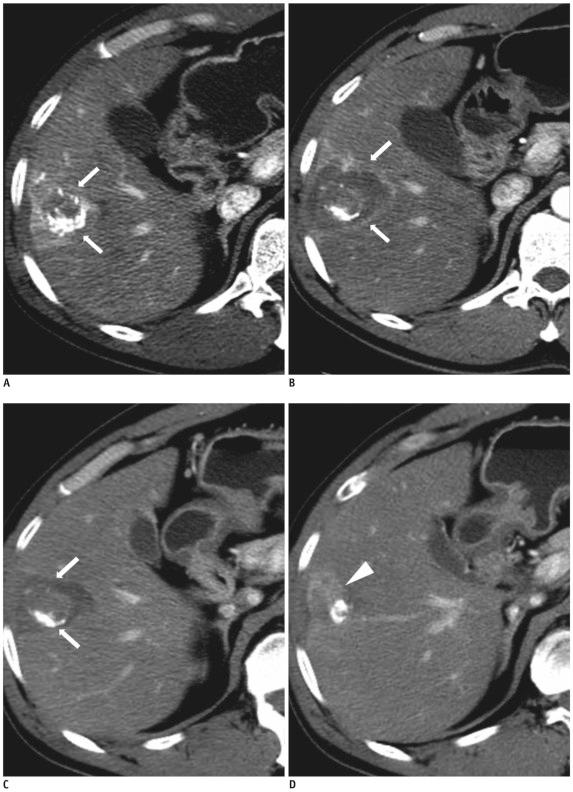

To evaluate the effectiveness of ultrasound-guided radiofrequency (RF) ablation in patients with incompletely treated hepatocellular carcinoma (HCC) after transcatheter arterial chemoembolization (TACE) and to evaluate possible prognostic factors for this therapy.

Thirty nine patients with incompletely treated single HCC (≤ 5 cm) after TACE were treated with RF ablation. All patients were evaluated for complete tumor ablation rate, local recurrence-free rate, overall survival rate, and complications. Local recurrence-free rate and overall survival rate were calculated using the Kaplan-Meier method. The possible prognostic factors of local recurrence-free rate and survival rate were analyzed using Cox proportional-hazards regression model.

The complete tumor ablation rate was 92.3%. Local recurrence-free rates for 1-, 2-, 3-, and 5-years were 81.7%, 63.1%, 53.6%, and 35.7%, respectively. One-, 2-, 3-, and 5-year overall survival rates were 96.9%, 82.9%, 67.8%, and 48.4%, respectively. Among prognostic factors included in the analysis, only tumor diameter (≤ 2 cm versus > 2 cm) was statistically significant in terms of predicting local recurrence. Complications were observed in two patients, one with liver abscess and the other with portal venous thrombosis.

Ultrasound-guided RF ablation could be effective and safe in treating incompletely treated HCC after TACE. The diameter of HCC was a significant prognostic factor for local recurrence.